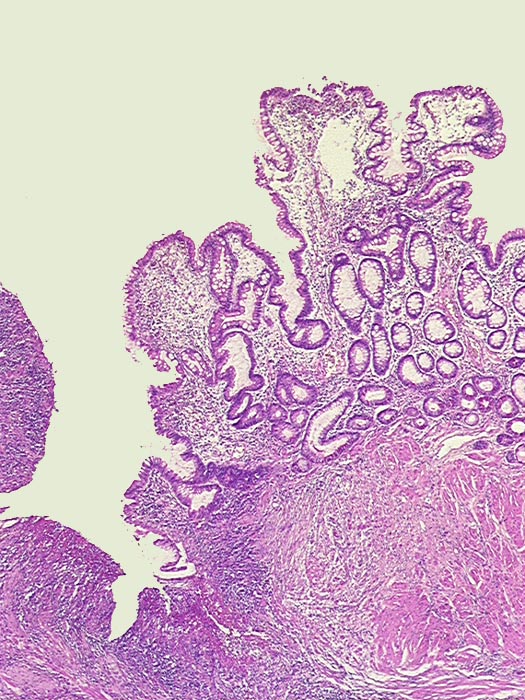

Fissurales Ulkus bei floridem Morbus Crohn

Ileum terminal

Links das tiefreichende Ulkus. Rechts davon hyperplastische Dünndarmschleimhaut (makroskopisch Pflastersteinrelief).

Stenose des terminalen Ileums mit chronischem Subileus